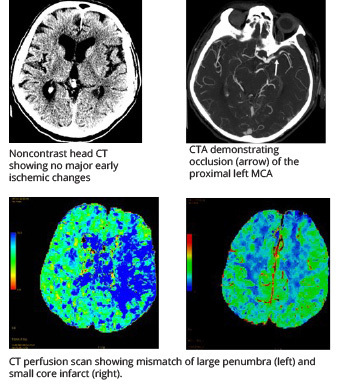

Neuroimaging is used in the selection of patients for MT. Various modalities can be employed to assess not only for the presence of an LVO, but also to evaluate which patients are likely to see benefit from the procedure. (See Figure 1.)

Figure 1. Neurovascular Imaging for an Acute Ischemic Stroke Patient Undergoing Evaluation for Endovascular Intervention |

Case: An 84-year-old man with hypertension, coronary artery disease status post-bypass, and stenting presented to the emergency department with acute onset aphasia and right hemiparesis. The initial NIHSS was 12. Noncontrast head CT ruled out hemorrhage and found no early ischemic changes (ASPECTS 10). CTA demonstrated an occlusion of the proximal MCA. The patient was outside of the window for IV tPA. Groin puncture occurred within six hours of onset. The interventionalist achieved full recanalization with a single pass of a stent-retriever device. The patient was found to have atrial fibrillation as the cause of his stroke. He was discharged home with full strength and minor aphasia. |

NIHSS: National Institutes of Health Stroke Scale; ASPECTS: Alberta Stroke Program Early Computed Tomography Score; CTA: computed tomography angiogram; MCA: middle cerebral artery; IV: intravenous; tPA: alteplase Source: Lerario MP, Segal A. Acute ischemic stroke: Focus on reperfusion. Emerg Med Rep 2016;37:106-107. |

Non-contrast computed tomography (NCCT) is a widely available, noninvasive, and fast study that is performed for all patients with suspected stroke. It is sensitive in detecting intracranial hemorrhage, but it often is normal for the first few hours after an acute ischemic stroke.24 The loss of gray-white matter differentiation may be seen as an early sign in some cases and can be optimized using stroke windows.25 NCCT is not sensitive in identifying an LVO; however, an asymmetric hyperdensity overlying the cerebral vasculature may be seen in some cases, which, when present, is highly specific.26

Computed tomography angiography (CTA) of the head and neck is used to evaluate LVO and localize the occlusion to determine if it is amenable to MT. CTA has high sensitivity and specificity in identifying an LVO.27 The neck is included to evaluate for abnormalities that may have contributed, such as stenosis, dissection, and vasculitis.

Computed tomography perfusion (CTP) is used in acute stroke to assess for perfusion mismatch indicated by hypoperfusion of cerebral tissues. It has a sensitivity and specificity similar to that of CTA. It can be used to identify and differentiate infarcted and irreversibly damaged areas of the brain (core infarct) from areas that potentially are salvageable (penumbra). The penumbra is the target for reperfusion via MT. Patients with a lower mismatch ratio between penumbra and ischemic core (e.g., < 1.8) are unlikely to see benefit from reperfusion therapy. Those with a large core also are at risk of hemorrhagic conversion after reperfusion.28 It is important to note that other conditions, such as vasospasm, chronic infarcts, and microvascular ischemic changes, also can show decreased perfusion on CTP.29